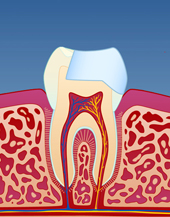

Kroneterapi

Dersom tannen er veldig svekket, kan det vise seg at en stor fyllingsoppbygging ikke vil være sterk nok. Dette kan særlig gjelde for rotfylte tenner. Da kan en keramisk krone (porselenskrone) være et bedre alternativ. Å få fremstilt en keramisk krone innebærer at tannen slipes og formes til slik at en porselenstann kan sementeres utenpå.

Porselenstannen lages av en tanntekniker og er sterkere og penere i forhold til en vanlig fylling. Prosessen er imidlertid tidkrevende og teknisk vanskelig både for tannlegen og tannteknikeren. Det er derfor prisen for en krone er høyere enn for en vanlig fylling.